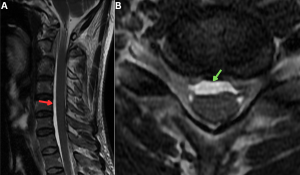

Fig 19: A 42-year-old with long-standing postural headaches and neck stiffness.

Figure A: Sagittal T2-weighted MRI showing anterior epidural collection (red arrow).

Figure B: Axial T2-weighted MRI demonstrating anterior epidural collection with smooth, rounded margins (green arrow), consistent with chronic spinal longitudinal extradural collection (SLEC).

In chronic SLEC-positive cases, persistent ventral epidural collections may compress the anterior horn cells and stretch the cervical nerve roots, resulting in progressive cord and root atrophy and clinically manifesting as bibrachial amyotrophy (15).

Fig 20: A 52-year-old man with a 6-month history of chronic orthostatic headache and progressive mid-thoracic discomfort, previously untreated for SIH.

Figure A: Axial T2-weighted image of the thoracic spine showing T2 hyperintensities in the region of anterior horn cells (red arrow) along with a T2 hyperintense anterior epidural fluid collection (green arrow).